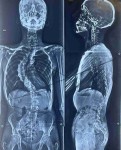

انزلاق غضروفي عنقي متعدد قبل وبعد الجراحة

تحدب بالفقرات الصدرية

اعوجاج مزدوج بالفقرات الصدرية والقطنية

حالة اعوجاج بالفقرات الصدرية